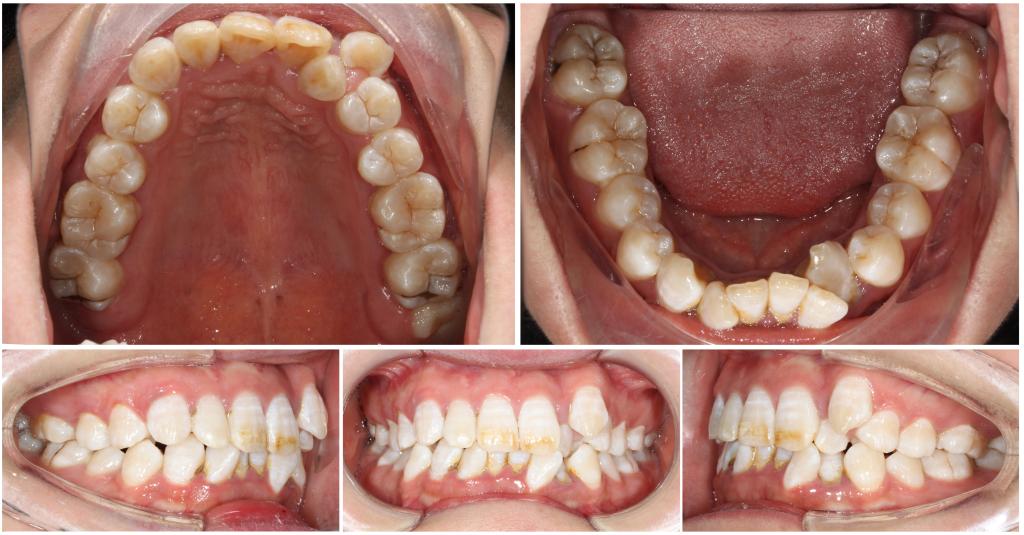

1. 牙齿模型:正畸模型是患者牙、牙弓、牙槽等形态及上下颌牙关系的精确复制。

2. 口内像及面部相片:用照片的形式直观记录矫治前、中、后各个阶段面部及牙状态是正畸检查诊断的重要一环。